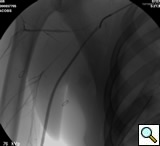

After traversing the vessel with a Glidewire and visualizing the wire conforming to normal arterial profile down into the distal extremity, it is necessary to change out the sheath for a long 8F sheath. It is necessary to advance the sheath into the proximal subclavian artery. To increase support we change out the guide wire for a stiffer Amplatz® (Boston Scientific Corp. Natick, MA) Guidewire extending down into the arm. Next, we perform selective views of the

transected artery visualizing the pseudoaneurysm (Figure 2). A Viabahn covered stent (W.L. Gore & Associates, Flagstaff, AZ) is chosen for the appropriate size of the native vessel being careful not to oversize the stent graft. The stent graft is advanced across the lesion. Selective angiograms through the sheath may be performed to choose correct placement and appropriate landing zones. The stent graft is deployed under fluoroscopic visualization. Next, we utilize an appropriate sized 10 mm low pressure balloon to “iron out the edges” of the stent and bring it up to profile of the artery (Figure 3). Next, completion angiograms are performed to rule out endoleak and complete exclusion of the pseudoaneurysm, as well as to confirm distal runoff to the forearm and palmar branches of the extremity (Figure 4).